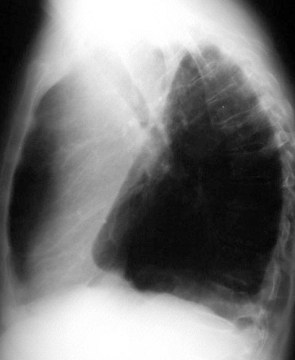

Signo de colapso del lóbulo superior izquierdo en la radiografía posteroanterior de tórax. Consiste en la hiperclaridad o lámina aérea alrededor del arco aórtico (flechas) producida por la hiperinsuflación del lóbulo inferior izquierdo, que asciende hasta el vértice pulmonar. El segmento 6 contacta con la parte posterior del botón aórtico, permitiendo que éste sea visualizado con gran nitidez.

La proyección lateral confirma el colapso del lóbulo superior izquierdo, manifestado por el aumento de densidad anterosuperior, el desplazamiento anterior de la cisura mayor y la hiperinsuflación del lóbulo inferior.